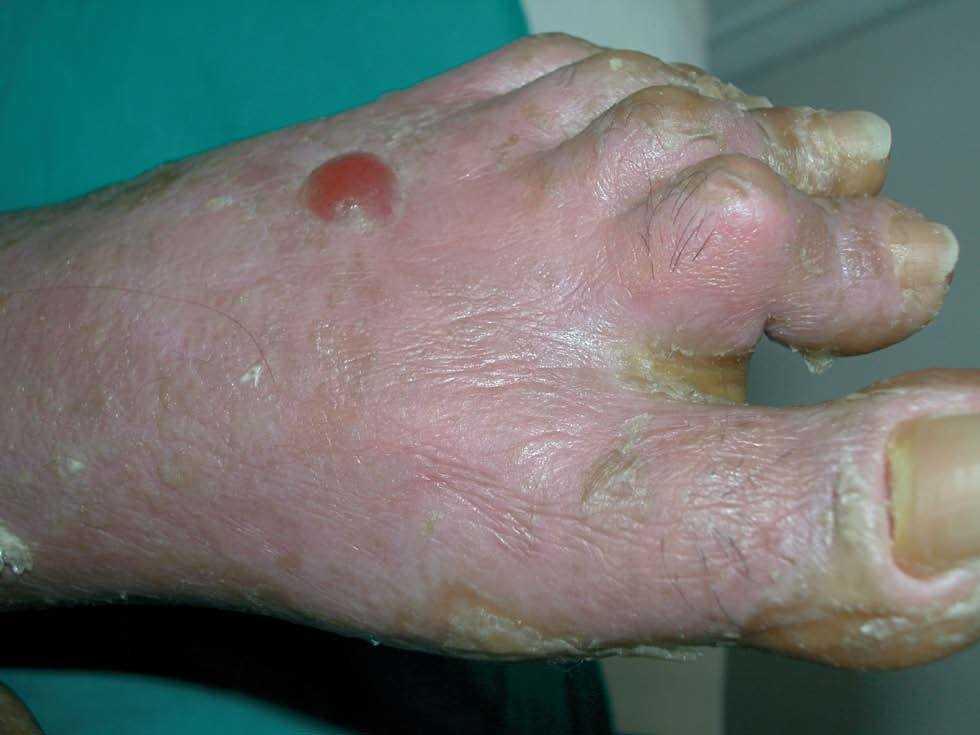

Existían 4 tipos de lesiones cutáneas: en antebrazos, muslos y piernas las lesiones consistían en pápulas planas poligonales confluentes con brillo blanquecino (fig. 1). En manos y pies, tanto en el área dorsal como palmoplantar, existía una hiperqueratosis con descamación foliácea, con edema severo subyacente (fig. 2). En el resto de las extremidades y en el tronco existía un eritema descamativo generalizado con tinte violáceo (fig. 3). Por último, se encontraron ampollas tensas en rodillas y dorso de pies, algunas de contenido hemorrágico (fig. 2). El signo de Nikolsky era negativo.

Fig. 2.—Ampolla tensa en el dorso del pie izquierdo.